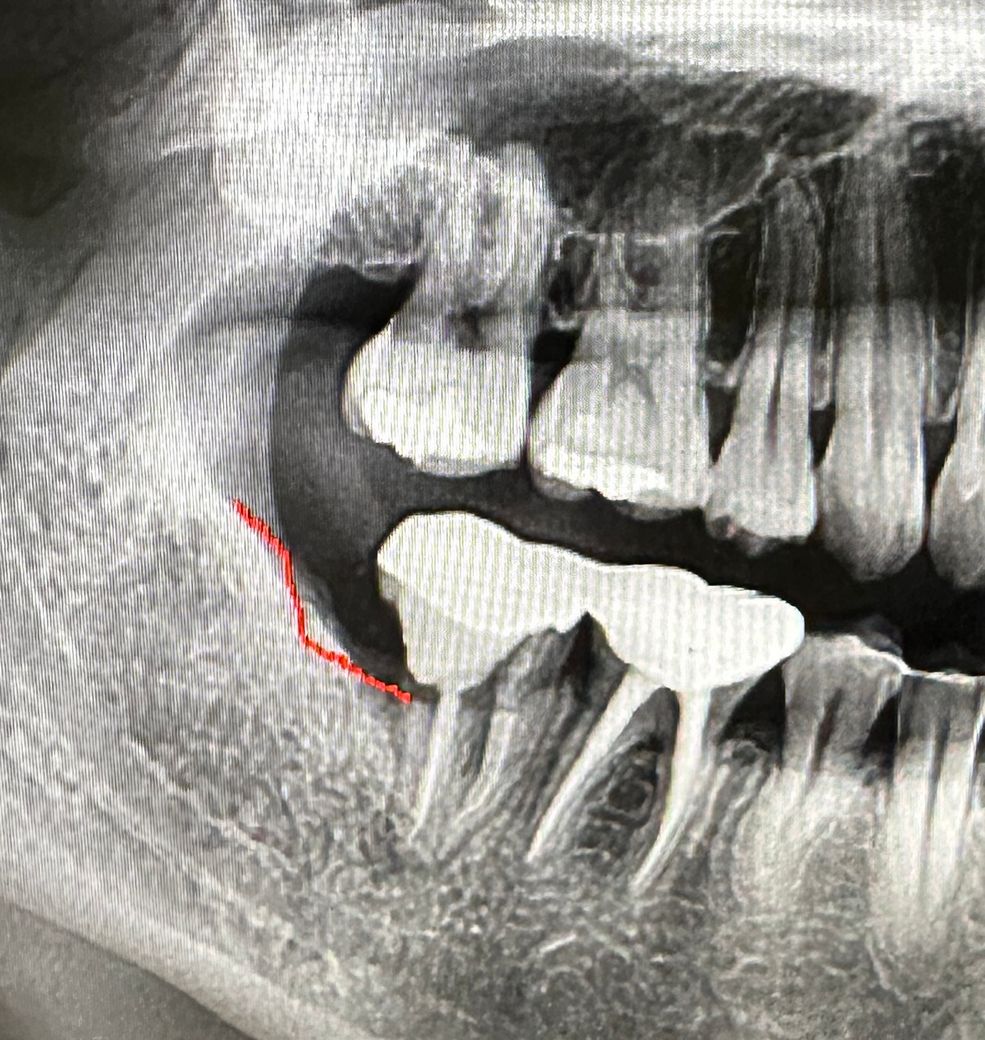

어금니 재신경치료 중인데 발치해야 될까요?

어금니가 너무 아파서 치과에 갔더니

10년전에 충치로 신경치료하고 금을 씌운 어금니 안에가 문제가 있는것 같다 하여

금 벗기고 안에 확인을 하니 어금니옆에 구멍쪽으로 찌꺼기들이 들어갔는지 구취가 날정도로 문제가 있었습니다

사진 보시면ㅠ 꼭 발치까지 가야될까요?

치아를 보존 할수있는 다른 방도는 없을까요?

사진으로 봤을 경우에는 충치가 생긴 부위가 잇몸 뿌리 쪽에 가깝게 있는 것으로 보입니다. 충치가 잇몸뼈 아래로 내려가게 되면 치아를 살릴 수 없는 경우가 생길 수 있습니다. 해당 부위는 건조가 안되기 때문에 깨끗하게 재료로 메꿀 수 없기 때문입니다

옆면이 썩어들어가서 떼운 상태는 치아 보존을 위해 불리한 상태입니다. 재신경치료를 일단 하는데까지 해보고 치아 상태를 재평가 해야 합니다. 발치에 대한 설명은 가능성을 언급한 것입니다.